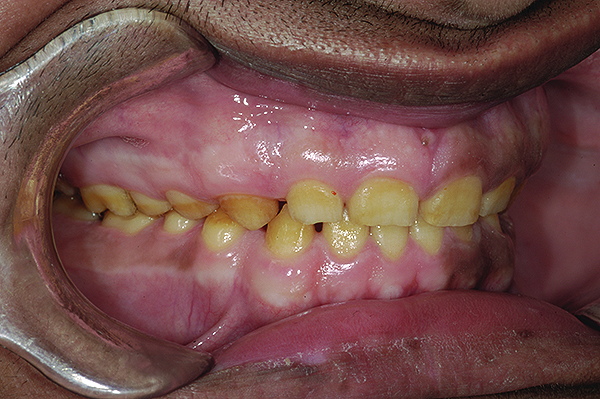

A thorough clinical examination and analysis were carried out to assess the esthetic and functional problems of the patient (Figure 2 through Figure 7). The medical history was non-contributory, except for mild leukoderma. Temporomandibular joint (TMJ) function was within normal range.

Figure 2. Preoperative 1:2 retracted frontal view.

Figure 2

Figure 3. Preoperative 1:2 retracted right lateral view.

Figure 3

Figure 4. Preoperative 1:2 retracted left lateral view.

Figure 4

Figure 5. Preoperative 1:1 retracted frontal view.

Figure 5